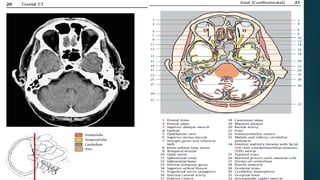

Este documento es el programa para un taller de imágenes del curso de emergencia 2015 impartido por el Dr. Víctor Delgado. El taller se centra en el uso de imágenes médicas para el diagnóstico y tratamiento de pacientes en coma traumático según la base de datos de Marshall. El Dr. Delgado es el único instructor repetido a lo largo del documento.